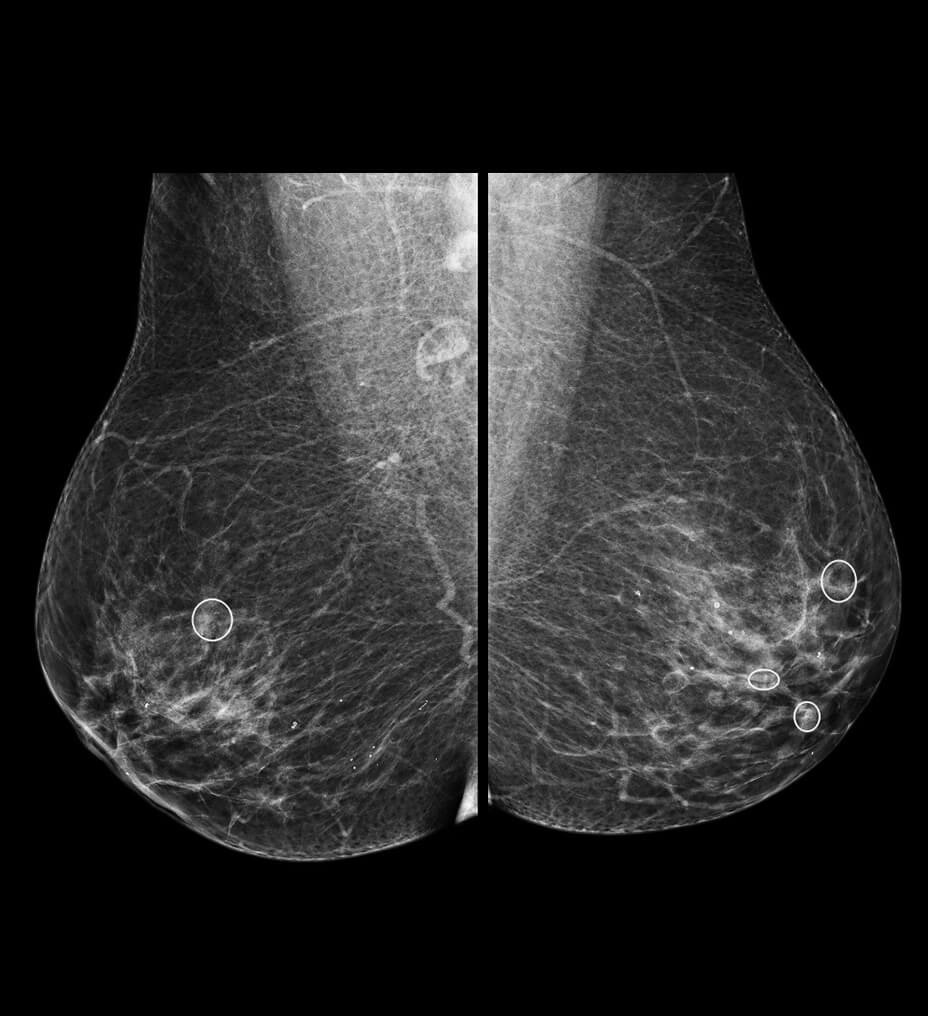

TrueFidelity DL + True Enhance DL

Better together

With the Revolution Ascend Platform, you can combine both of our AI-based imaging reconstruction technologies to create one stunning image. By combining True Enhance DL with TrueFidelity DL, you can achieve images that have less noise, enhanced sharpness and better noise texture than images obtained with ASiR-V.

True Enhance DL

Designed to enhance what matters

True Enhance DL is a deep learning-based processing method intended for contrast enhancement of single energy images. True Enhance DL uses a dedicated Deep Neural Network (DNN) trained to estimate monochromatic, 50 keV GSI images from single-energy X-ray. This technology brings four deep learning models that the user can choose depending on different contrast enhancement phases by clinical tasks.

TrueFidelity DL

Deep learning for a deeper understanding

TrueFidelity™ DL is our state-of-the-art image reconstruction technology that uses a DNN to generate high-definition, low-noise CT images. It produces images with exceptional sharpness, low-contrast image quality performance and your preferred noise texture, at the same dose.¹